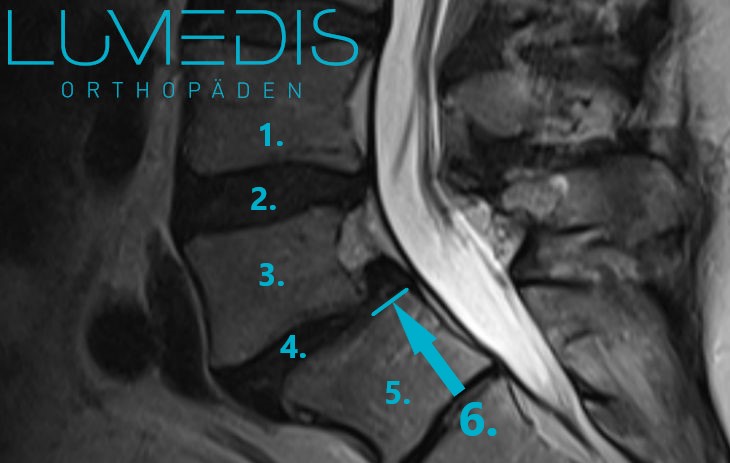

MRT der LWS (seitlich, T2) mit einem Bandscheibenvorfall L5/S1:

MRT der LWS (T2, seitlich)

Abbildung eines Bandscheibenvorfalls